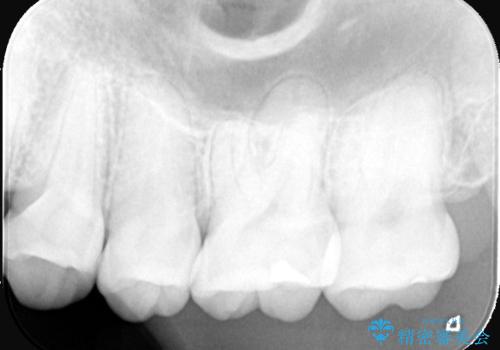

今回の治療では、虫歯の大きさや深さに応じて、異なるセラミック修復法を適用しました。

比較的軽度な虫歯には、セラミックインレー(詰め物)で対応し、健全な歯質を最大限に残しました。

進行した虫歯や歯の強度が低下している歯には、セラミッククラウン(被せ物)を選択し、歯全体を保護することで破折を防ぎました。